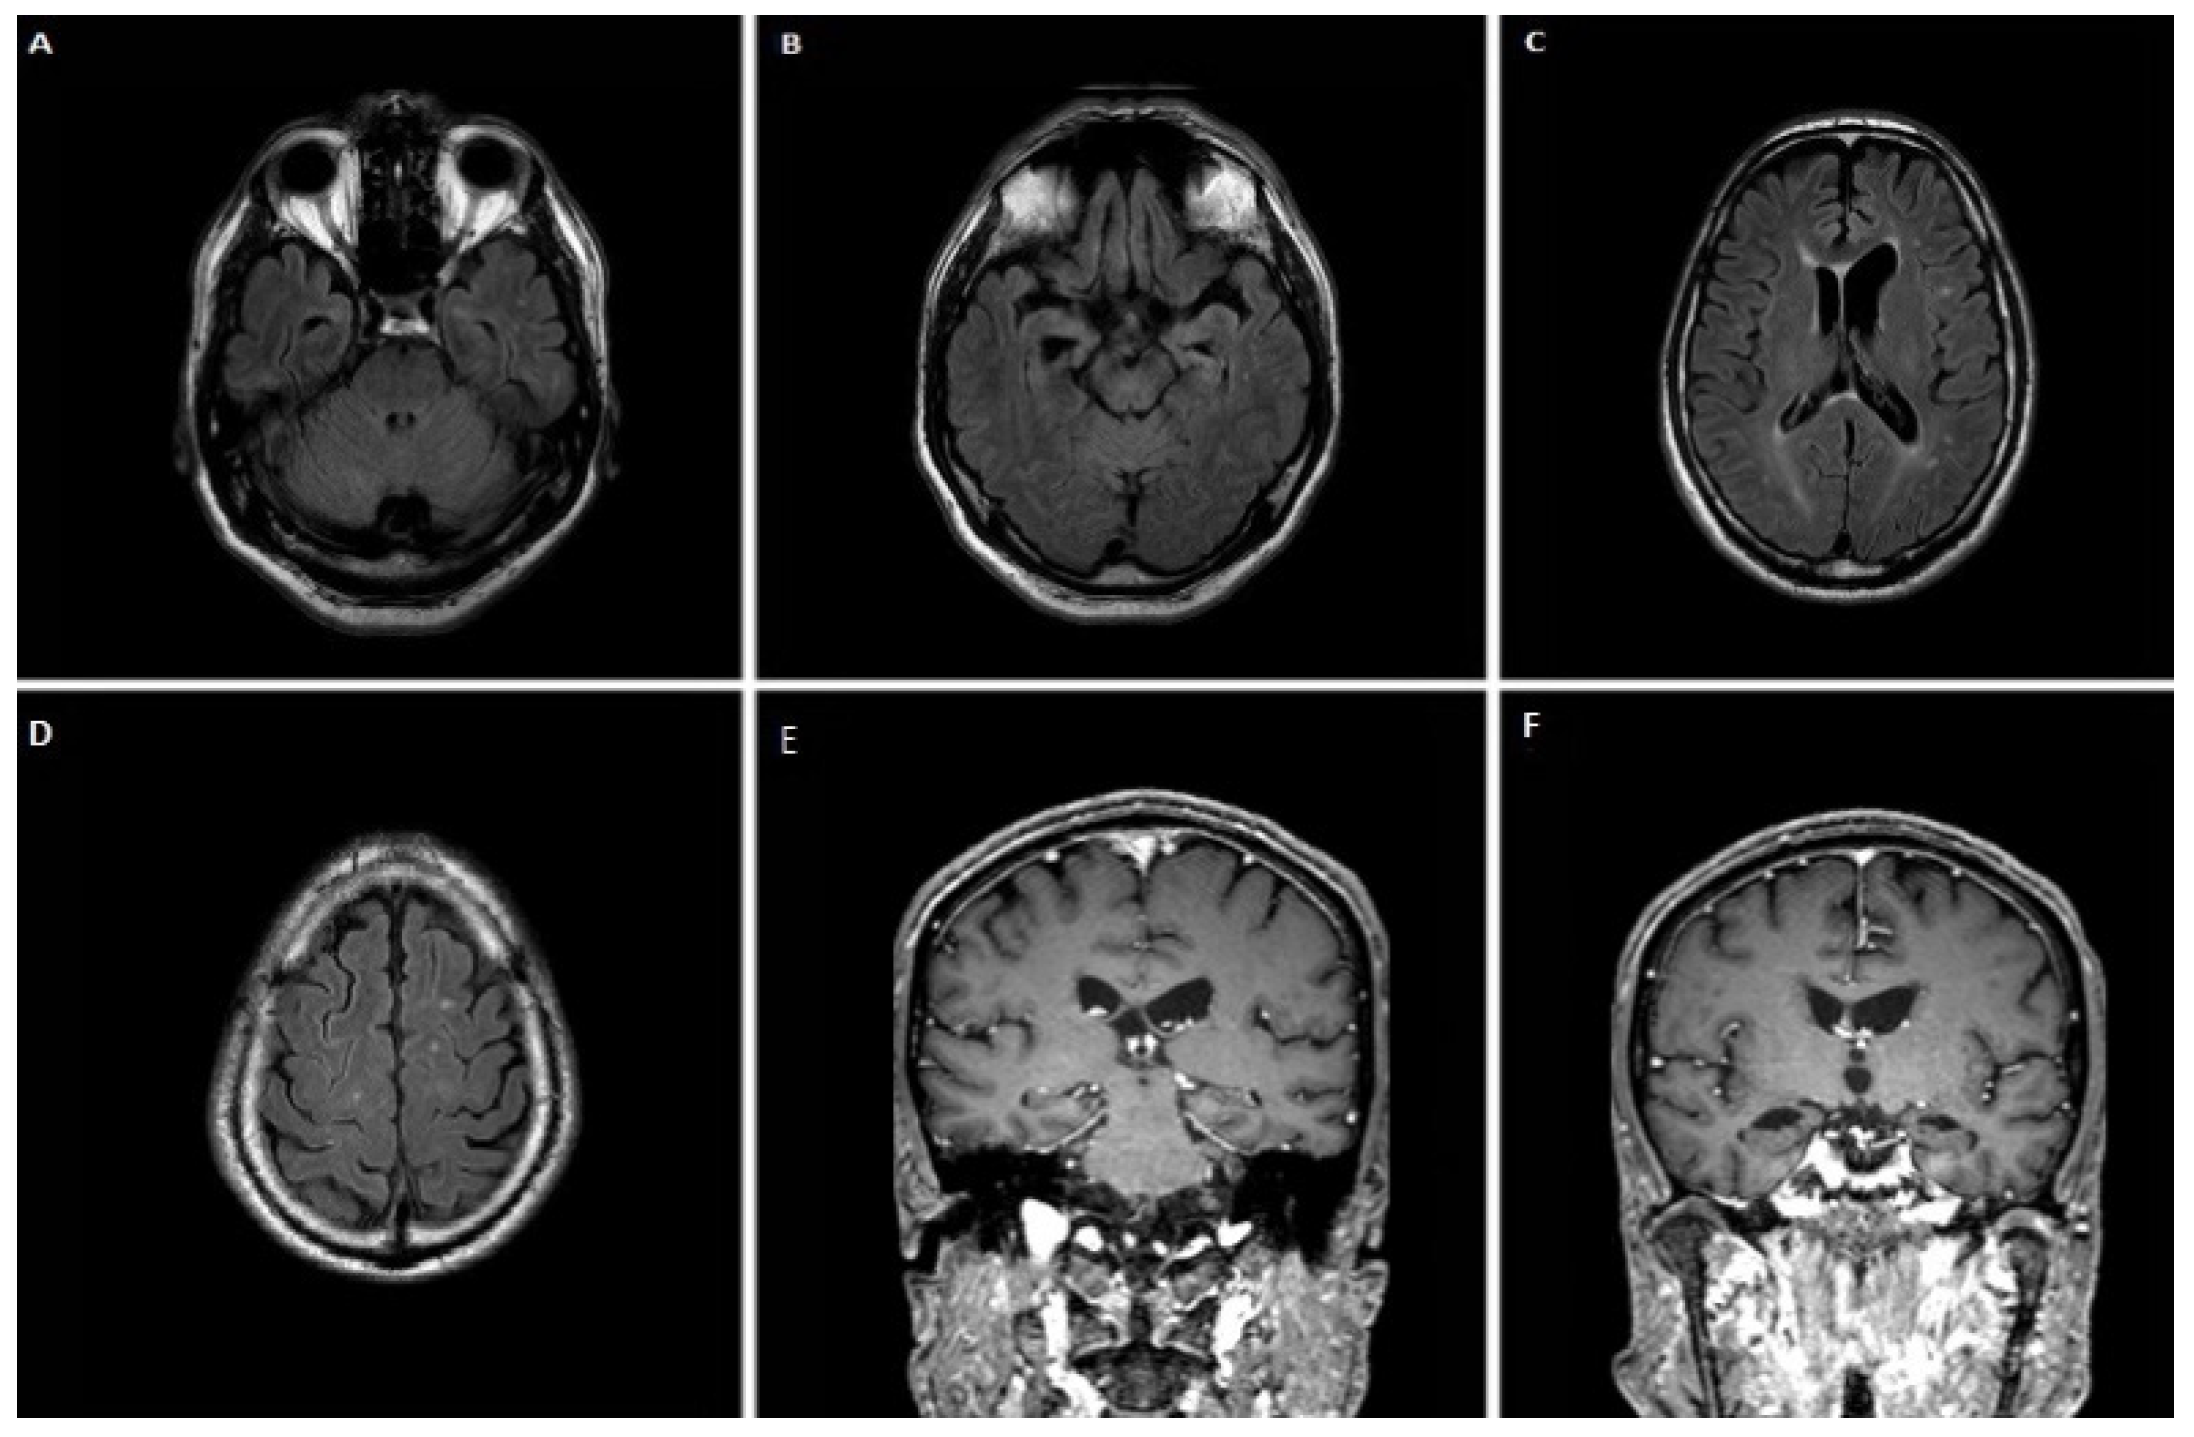

3.1.1. Case 1

3.1.2. Case 2

3.1.3. Case 3

3.1.4. Case 4

3.1.5. Case 5

3.1.6. Case 6